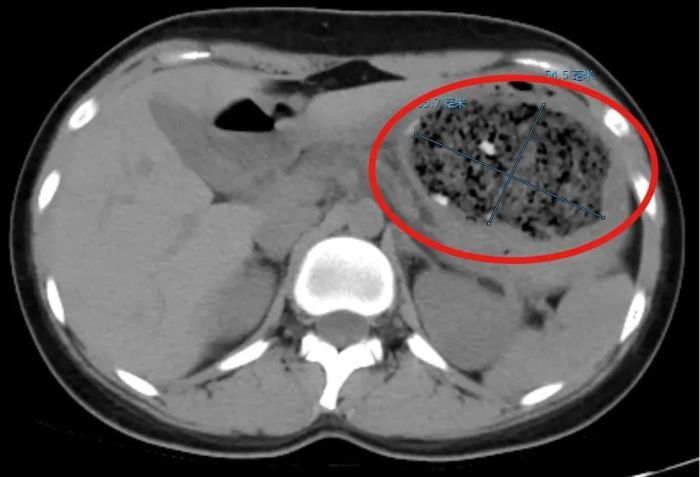

接诊的消化内科副主任杨晶简单问了病史后,给倩倩安排了腹部CT平扫检查,结果发现一个8.6cm×5.5cm左右的巨大的异物把她的胃塞得满满当当。

在进一步胃镜检查后,杨晶发现,倩倩胃里面的结石体积庞大,几乎不留什么空隙,这使得常规的异物圈套器无法施展。